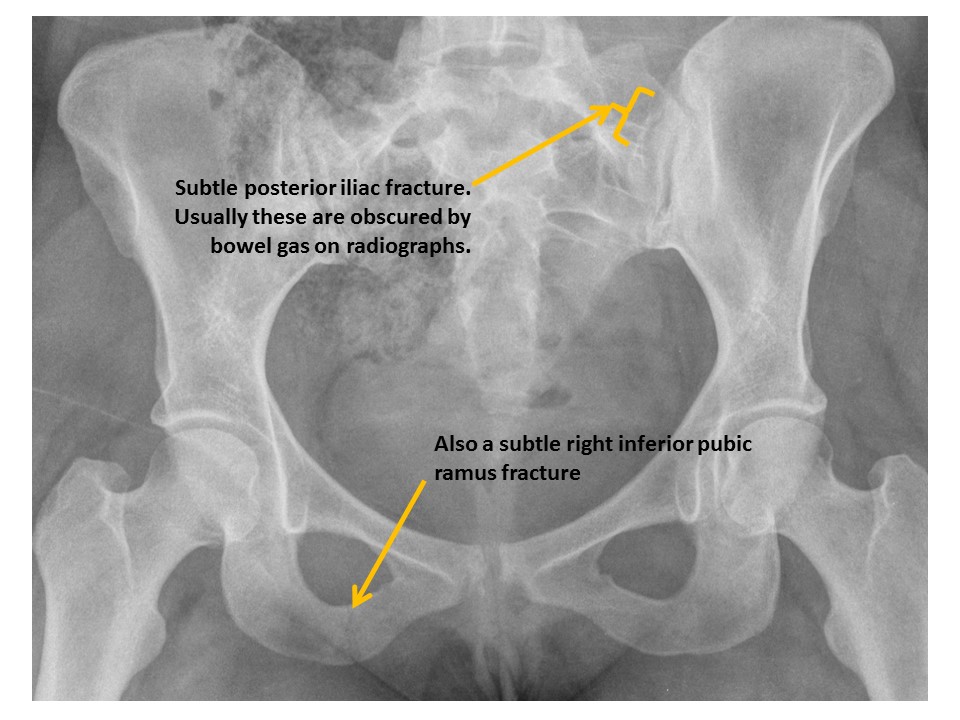

SACRUM and SACROILIAC JOINTS

There are displaced fractures or disrupted/asymmetric foraminal arcs. [Yes/No]

The sacroiliac joints are widened and asymmetric. [Yes/No]

There is malalignment at the inferior margin of the sacroiliac joints. [Yes/No]

PUBIC SYMPHYSIS and RAMI

There is a pubic ramus fracture. [Yes/No]

ILIAC BONES

Posterior iliac bone fractures are present. [Yes/No]